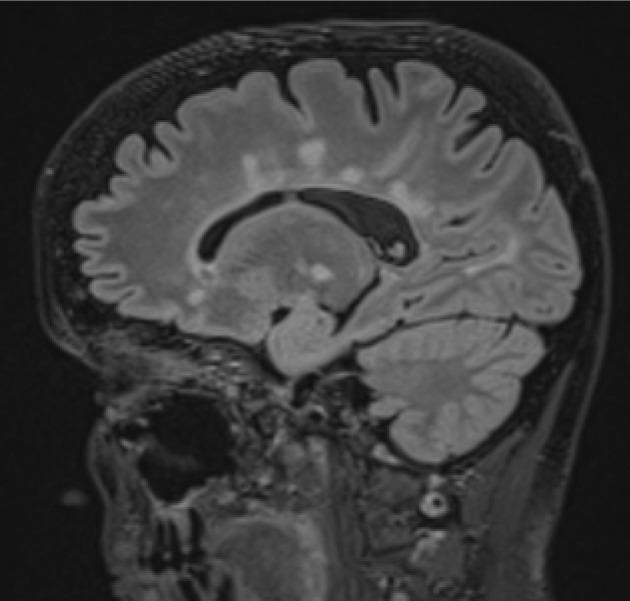

Multiple sclerosis (MS) is a chronic, demyelinating disease affecting the central nervous system. Diagnosis of MS is based on the proof of disease dissemination in time (DIT) and dissemination in space (DIS) and excluding other disorders that can mimic multiple sclerosis in laboratory tests and clinical manifestation. Over the years the diagnostic criteria have evolved; the introduction of magnetic resonance in the McDonald's 2001 criteria was revolutionary. Since then, the criteria have been modified up to the currently used McDonald 2017. The aim of this review is to analyse the 2017 McDonald criteria, assess what has changed from the 2010 criteria, and present the impact of revised criteria on rapid and accurate diagnosis of MS. The main differences are as follows: inclusion of oligoclonal bands in cerebrospinal fluid as a DIT criterion, and symptomatic and cortical lesions in magnetic resonance imaging are counted in the determination of DIS and DIT. We present also the newest recommendations of the Polish Medical Society of Radiology and the Polish Society of Neurology and international group of North American Imaging in Multiple Sclerosis and Consortium of Multiple Sclerosis Centers, as well as future directions for further investigations. A proper diagnosis is crucial for the patient's quality of life, to give the possibility of early treatment, and to help avoid misdiagnosis and unnecessary therapy.

多发性硬化症(MS)是一种影响中枢神经系统的慢性脱髓鞘疾病。MS的诊断基于疾病时间上的播散(DIT)和空间上的播散(DIS)的证据,并在实验室检查和临床表现中排除其他可模拟多发性硬化症的疾病。多年来,诊断标准不断演变;2001年麦克唐纳标准中引入磁共振成像具有革命性意义。从那时起,该标准不断修订,直至目前使用的2017年麦克唐纳标准。本综述的目的是分析2017年麦克唐纳标准,评估与2010年标准相比有哪些变化,并阐述修订后的标准对MS快速准确诊断的影响。主要差异如下:将脑脊液中的寡克隆带纳入作为DIT标准,磁共振成像中的症状性和皮质病变在DIS和DIT的判定中予以计数。我们还介绍了波兰放射医学学会、波兰神经病学学会以及北美多发性硬化症影像学国际组和多发性硬化症中心联盟的最新建议,以及进一步研究的未来方向。正确的诊断对于患者的生活质量、给予早期治疗的可能性以及帮助避免误诊和不必要的治疗至关重要。